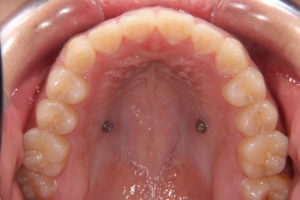

今回は八重歯の非抜歯症例です。

①主訴 八重歯

②診断名 叢生

③年齢 11歳

④治療に用いた主な装置マルチブラテット装置 歯科矯正用アンカースクリュー

⑤抜歯部位 なし

⑥治療期間 3年

術後 八重歯がなくなったので、笑った時の印象もだいぶかわりました。

はじめは間は前から見えないリンガルアーチを使って治療し、小6の夏から

マルチブラケット装置と歯科矯正用アンカースクリューを用いて治療しました。

中2の終わり頃に装置を外せました。